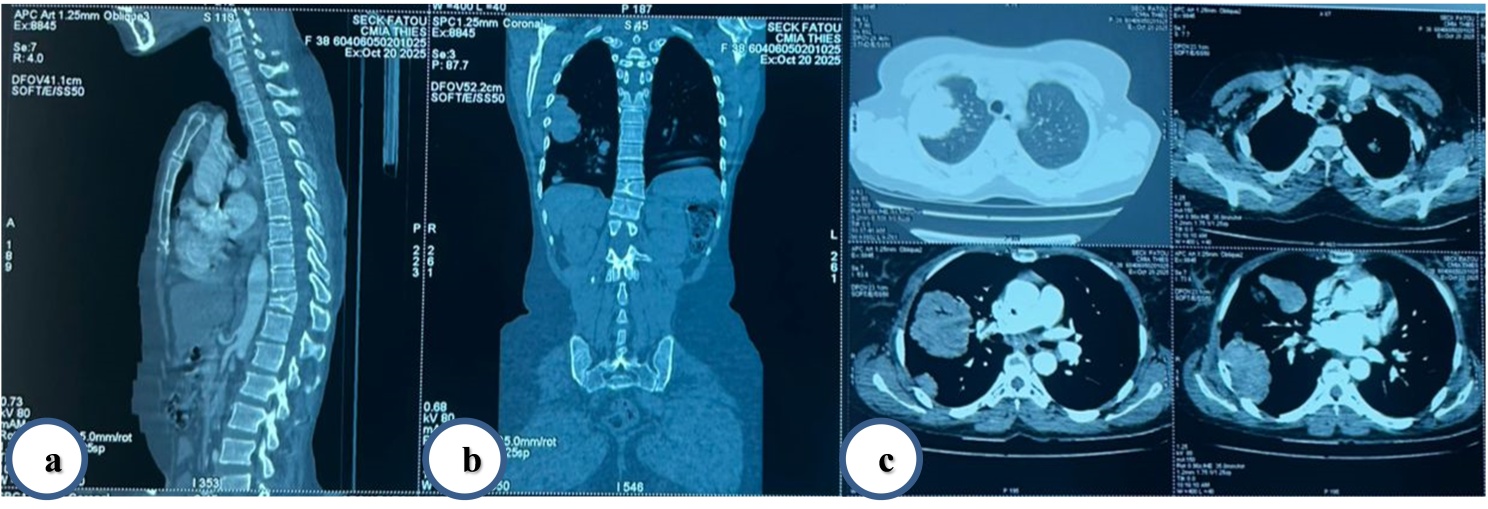

Cervico-thoraco-abdominopelvic CT confirmed multiple bilateral pulmonary nodules without local recurrence or other metastases. Multiple bilateral pulmonary metastases are demonstrated in Figure 3.

Figure 3. CT scan (October 20, 2025) (a) Sagittal, (b) Coronal, and (c) Axial sections showing multiple bilateral pulmonary metastases.

Cervico-thoraco-abdominopelvic CT confirmed multiple bilateral pulmonary nodules without local recurrence or other metastases.